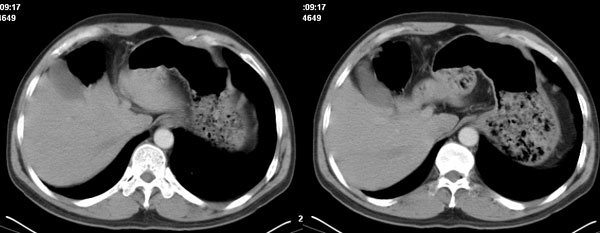

李**,男,46岁,便血1天入院,慢性贫血貌,腹平、软,剑突下压痛,肠鸣音稍活跃,hb大于1g/l,胃镜:慢性浅表性胃炎,b超:1肝内多发性占位 2腹腔内囊性肿块 ,肝内圆形影平扫ct值42.9,动脉期48.6,静脉期58.2,延迟期62.2

影像学表现:1 腹腔前中部、胰腺前方囊实性病灶(个人认为确定有否实性成分存在这是关键,涉及到鉴别诊断,如果是口服阳性造影剂则可明确左侧是不是小肠了),囊性部分囊壁不均,实性部分有强化,与小肠关系较密切,局部小肠受推移;与胰头、胃后壁均有脂肪间隙存在;2 胰腺无异常改变,胰周无渗出;3肝后段包膜下2个小圆形低密度灶,从图像和楼主提供的ct值来看有轻度强化,灶周无片状强化,不似单纯囊肿及肝癌、炎性病变表现;4 腹膜后及腹腔内无淋巴结肿大。

胰腺边界清晰,胰周筋膜不厚,胰周脂肪密度无明显增高;其前方囊实性病灶,边界清晰,增强后实性部分轻度强化;肝内多发边界清晰低密度影,增强后无明显强化(平扫ct值42.9,动脉期48.6,静脉期58.2,延迟期62.2)。

原因:胰头前方,前上腹部巨大囊实性肿物,与小肠关系密切,与胰头及胃壁之间脂肪间隙存在,囊壁不均匀,部分强化,占位效应明显,小肠上段扩张,十二指肠及胃腔内大量食物存留,说明上消化道有部分梗阻。因此,考虑来源于肠道的肿瘤。再结合其病史及肝内改变,这样考虑更有道理。